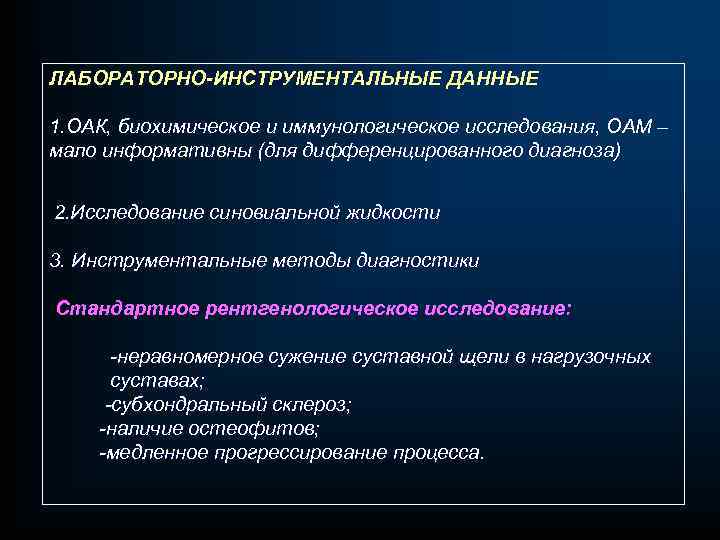

ЛАБОРАТОРНО-ИНСТРУМЕНТАЛЬНЫЕ ДАННЫЕ 1. ОАК, биохимическое и иммунологическое исследования, ОАМ – мало информативны (для дифференцированного диагноза) 2. Исследование синовиальной жидкости 3. Инструментальные методы диагностики Стандартное рентгенологическое исследование: -неравномерное сужение суставной щели в нагрузочных суставах; -субхондральный склероз; -наличие остеофитов; -медленное прогрессирование процесса.

ЛАБОРАТОРНО-ИНСТРУМЕНТАЛЬНЫЕ ДАННЫЕ 1. ОАК, биохимическое и иммунологическое исследования, ОАМ – мало информативны (для дифференцированного диагноза) 2. Исследование синовиальной жидкости 3. Инструментальные методы диагностики Стандартное рентгенологическое исследование: -неравномерное сужение суставной щели в нагрузочных суставах; -субхондральный склероз; -наличие остеофитов; -медленное прогрессирование процесса.